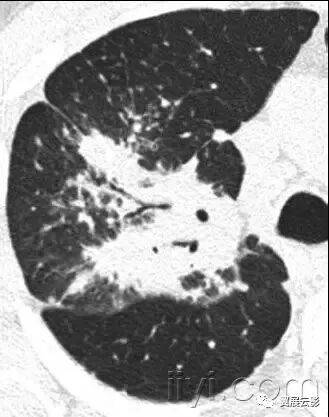

十九、肺实变:

病理学:肺实变是指渗出,或者其他疾病成分替代肺泡内气体,导致肺实变。

平片和CT:肺实变表现为肺实质密度的均匀一致性增高,导致肺血管和气道壁边缘不清。有时可见含气支气管征。只有在极少数的情况下,肺实变的密度变化有助于鉴别诊断,例如脂性肺炎是密度减低,胺碘酮中毒时密度增高。

图示为多灶性的肺实变。